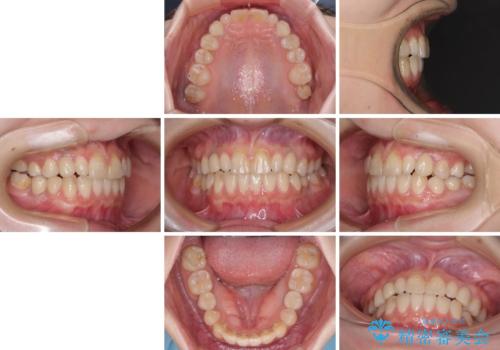

欠損と残存乳歯 矯正治療とインプラント治療

- 残存した乳歯や歯の欠損、歯並びを気にして来院された患者様です。

乳歯を残した状態は予後がよくないこと、矯正治療と補綴治療を総合的に進めていきたいとのことで、インビザラインによる矯正治療とインプラント補綴治療を並行して進めていくこととしました。